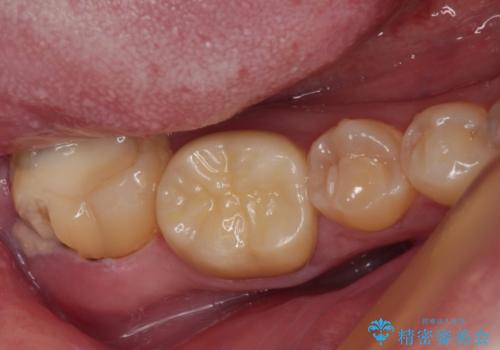

検査で見つかった虫歯 セラミッククラウンでの治療

担当医 岡田康成